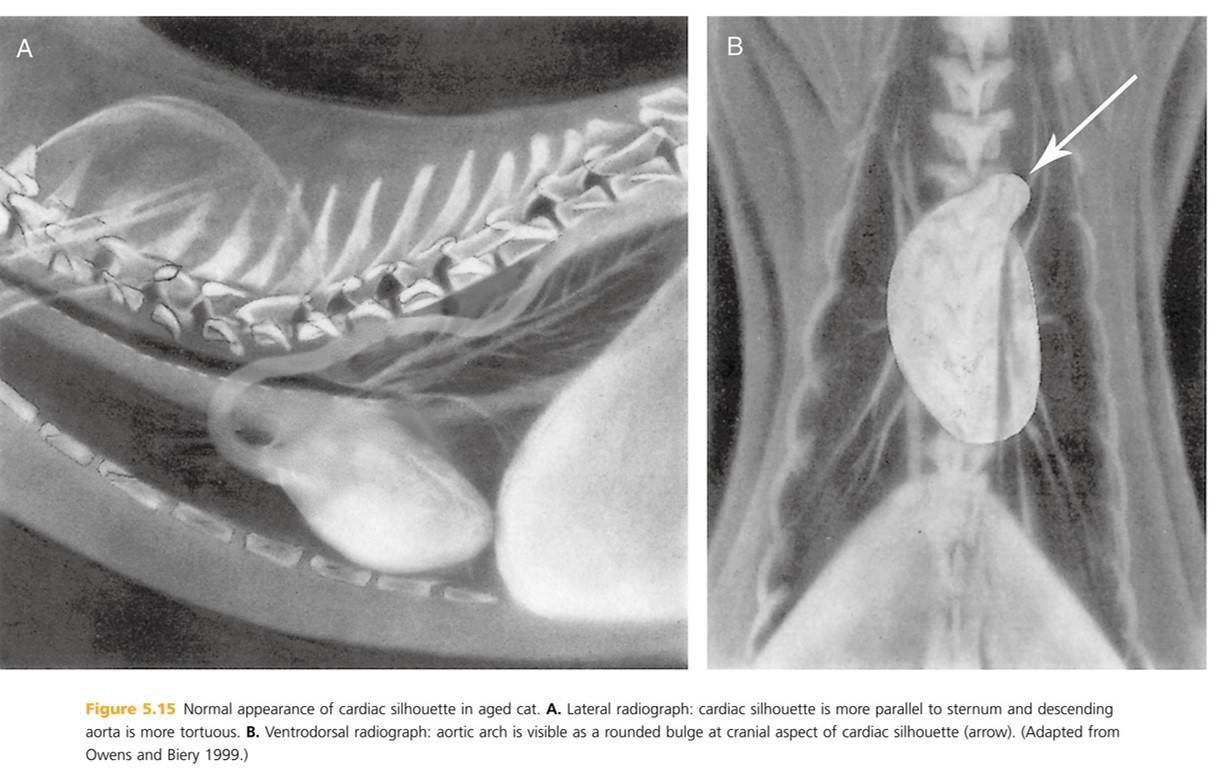

A cat cardiac silhouette radiograph is _____ at the crainal and caudal (compaired to a dog) and ends and appears to have a “_____” shape. The position of the apex is more _____ than a dogs, usually located on or left of midline but sometimes right of midline. In older cats, the cardiac silhouette is more ______ in position.

thinner

lemon

vairable

horizontal (more parallel with the sternum)

(picture A)

In cats, the width of the cardiac silhouette on a lateral radiograph is ___ intercoastal (b/t ribs) spaces. Width on lateral rad is ____ the width of the thoracic cavity.

2

1/2 - a dog is 2/3 the width of the thoracic cavity.

How does the caudal trachea differ in the cardiac silhouette of a cat vs. a dog?

Cat tracheas DO NOT bend ventrally at the heart base.

Dog traches DO curve slightly ventral tat the heart base

Older cats loose the elasticity of the aortic wall resulting in an altered appearance to cardiovascular structures. The heart moves more ____ to the sternum and the aortic arch b/c more prominent (described as “____” or “_____”) and may be mistaken for a cranial mediastinal or pulmonary mass on (_____ radiographs). On _____ radiographs, the desecending aorta appears more tortuous, wavy , or redundant

parallel

Kinked or knuckled

VD/DV- (B)

lateral - (A) BTW, hypertension can also result in a more tortuous descending aorta